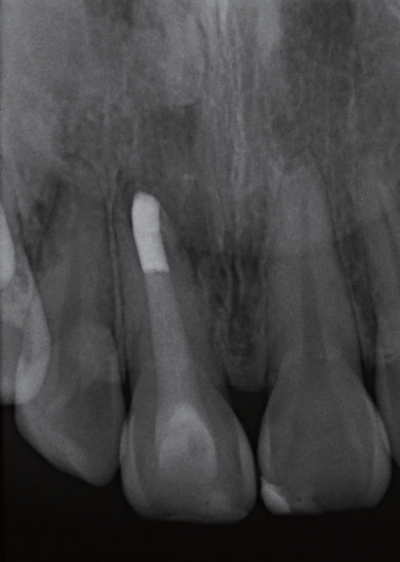

影像学检查   X线片显示11根尖尚未闭合(或根尖已经吸收),且根管宽大,可见根尖有一约8×10 mm的放射性阴影,周边牙槽骨明显缺损。询问患者自述曾经摔倒过,11受到撞击,不记得具体细节。

诊断与治疗计划   对比11 和12(图2)以及11和21(图3),11 的牙根长度较短,其根尖已出现阴影,按正常发育,11的根管应该不会如此宽大。因而推测患者在7~8 岁时,11应该曾经受到强烈撞击,导致牙髓坏死,使得根管没有继续钙化沉积,造成如今管壁相对较为单薄、根尖仍未完全闭合的情形。因而建议可在不给予局部麻醉下进行11开髓,进一步检查根管内部牙髓组织的实际状态。同时借助显微镜辅助进行根管治疗。

图2 对照12,11 根尖未闭合,牙根发育不全,且根尖周出现放射性阴影

牙胶尖什么颜色MTA的临床应用——陈志平教授_https://www.jmylbn.com_新闻资讯_第3张

图3 11 根管过于宽大,管壁略显薄弱,牙根长度较短